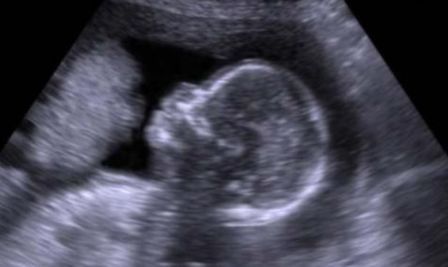

فحص المرأة الحامل بالامواج فوق الصوتية الايكو